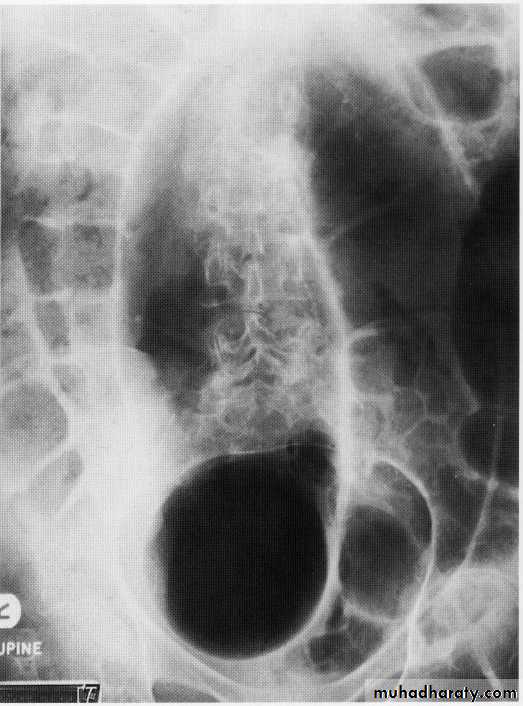

SB obstruct.